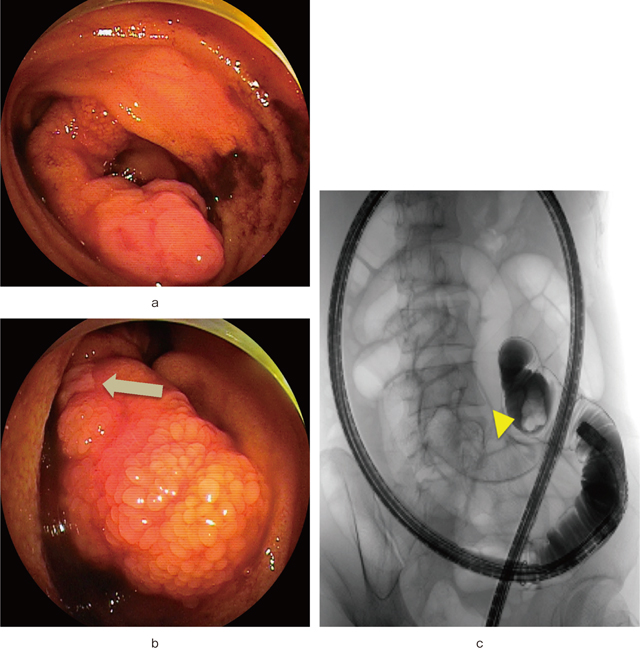

入院後経過:年齢やエピソード,出血シンチグラフィの結果からメッケル憩室を疑い,転院後直ちにメッケル憩室シンチグラフィを施行したが,明らかな異常集積は認めなかった.さらに同日,経肛門的ダブルバルーン小腸内視鏡検査を施行したところ,バウヒン弁より40cm口側に表面が軽度発赤した顆粒状粘膜で覆われ,頂部に潰瘍を伴う約50mm大の有茎性ポリープ様の病変(Figure 3-a,b)を認め,頂部の潰瘍より2箇所生検を施行した.生検での感触は硬い腫瘍であった.また,同時に行った小腸ガストログラフィン造影では,頭部を有する有茎性のポリープを認めた(Figure 3-c).頂部に潰瘍を認めたことより出血源と推測し,鑑別診断としてinflammatory fibroid polyp(IFP)や小腸ポリープを考え,内視鏡的切除を予定した.しかし,頂部からの生検結果で2箇所とも異所性胃粘膜を認めた(Figure 4)こと,改めて病変部位,内視鏡像等を検討し直し,棍棒状の形態や表面の粗大顆粒状粘膜等が,これまで報告のあるメッケル憩室内翻症と酷似していることより,小腸ポリープではなくメッケル憩室内翻症との術前診断で,当院外科にて腹腔鏡下回腸部分切除術が施行された.なお術前に,他病変除外のためにカプセル内視鏡も施行したが内翻したメッケル憩室の頭部を認める以外に潰瘍やポリープなど出血源となる病変は認めなかった.切除標本肉眼所見では,回腸内腔に突出する径15mm,長さ50mmの棍棒状の隆起性病変を認めた(Figure 5).病理組織学的にも病変の表面は正常の小腸粘膜に覆われており,腸管の全層を有する真性憩室の内翻であった.また,先端部で胃底腺粘膜組織が見られ,その近傍の筋層から漿膜下には膵組織も認めメッケル憩室内翻症に矛盾しない所見であった.術後経過良好につき退院となった.以後外来で経過観察し,貧血の進行等認めず約1カ月後に終診となっている.

経肛門ダブルバルーン小腸内視鏡所見.

a:表面が軽度発赤した顆粒状粘膜で覆われる約50mm大の有茎性ポリープ様の隆起性病変.

b:(矢印)病変頂部に潰瘍を認める.

c:小腸内視鏡下造影.

直径20mm大の有茎性のポリープを認める(矢頭:頭部).